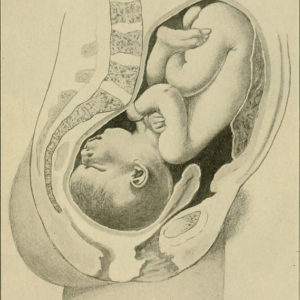

40 Semanas de Gestação

Sua 40ª semana começa

- Com 40 semanas de gestação já está pronto para vir ao mundo, apenas aguarda o sinal verde dos hormônios para dar ar da graça!

Com 40 semanas de gestação seu bebê já está pronto para vir ao mundo. Apenas aguarda o sinal verde dos hormônios para dar ar da graça! Com o desenvolvimento fetal totalmente completo, se prepara para conhecer finalmente esse mundo! Já tem todo seu corpo bem desenvolvido, incluindo os seus órgãos internos que já trabalham e fazem seu serviço da maneira esperada. Todos os seus sentidos fluem e respondem a estímulos e tudo será questão de tempo para se adequar e se aperfeiçoar com cada um deles. Seu pequeno coração bate rapidamente1, aproximadamente de 110 a 160 batimentos por minuto.

Nas 40 semanas de gravidez, seu sistema respiratório que estava em processo de amadurecimento nas últimas semanas já está pronto2. Assim que for cortado o cordão umbilical, o bebê começará a respirar sozinho. Seus olhos, que estavam acostumados a enxergar em uma distância limitada dentro do útero, agora terão que acostumar a enxergar objetos mais longe. Após o nascimento, ele ainda enxergará em torno de 30 cm do seu rosto, que equivale ao rosto da mamãe quando esta amamentando.

Cada bebê nasce com um peso e medida diferentes, mas nesta etapa das 40 semanas de gravidez é normal e esperado um bebê pesar em média 3,400 kg e medir 51 cm. Todos seus ossos estão bem firmes e rígidos exceto o do crânio que ainda não se fechou para facilitar a passagem no canal vaginal.